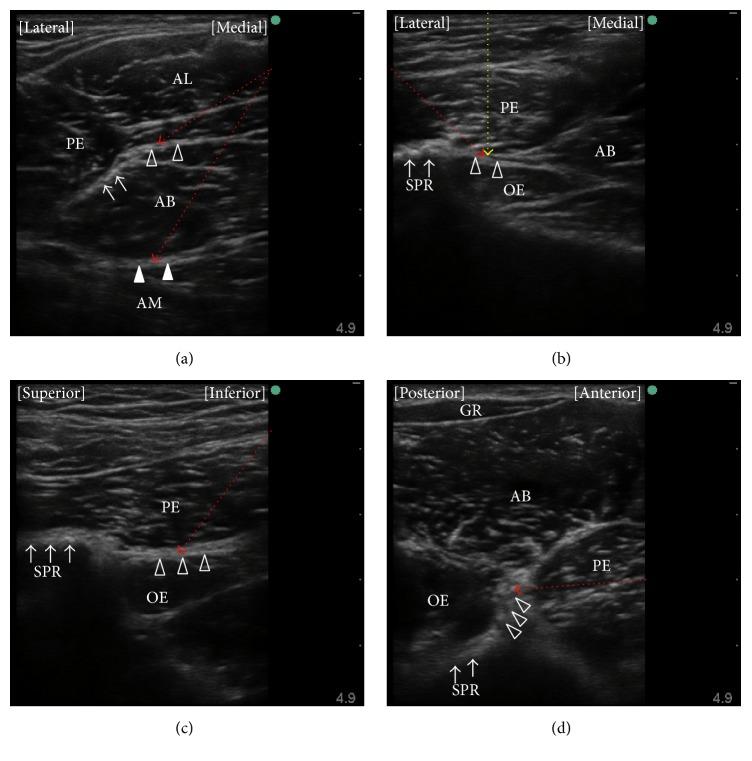

本综述概述了闭孔神经的解剖结构以及闭孔神经阻滞(ONB)的适应证。还讨论了超声引导下的ONB技术以及这些操作中尚未解决的问题。进行ONB可预防经尿道膀胱肿瘤切除术中大腿内收肌抽搐,为膝关节手术提供镇痛,治疗髋部疼痛,并改善持续性髋部内收肌痉挛。可使用多种超声引导下的ONB技术,可根据进针部位是远端还是近端进行分类。在远端进针方法中,将换能器置于腹股沟皱襞处;然后通过向神经各分支所在的筋膜间隙平面注射两次局部麻醉剂来阻滞神经的前支和后支。近端进针方法包括向耻骨肌和闭孔外肌之间的筋膜间隙平面单次注射局部麻醉剂。报道了几种涉及不同患者和换能器位置的近端进针方法。与远端进针方法相比,近端进针方法在减少局部麻醉剂剂量以及成功阻滞闭孔神经(包括髋关节支)方面可能更具优势。这一假设以及近端ONB技术之间的任何差异需要在未来的研究中进行探索。